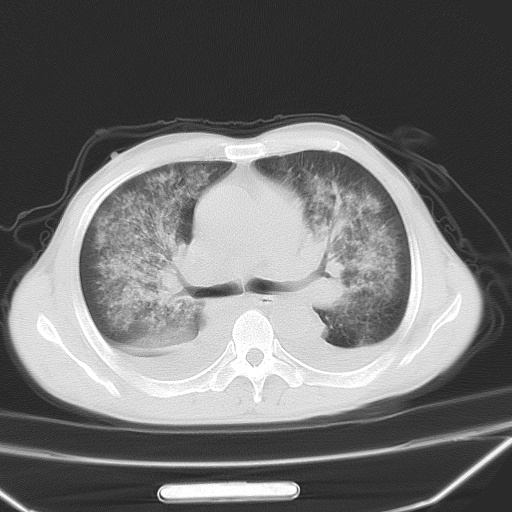

男、42岁、咯血3天。既往有甲亢、贫血、血尿蛋白尿史多年。血象:wbc:6.   中性粒:70.6%。

双肺堆成磨玻璃影,双测胸腔积液。考虑:肺水肿、间质性肺炎、真菌感染、ards、hiv感染、肺出血。

双肺野对称性磨玻璃影,分布于内中带,双侧胸水,患者有咯血。

1、间质性肺水肿;2、结合临床病史及实验室检查,考虑为肺出血肾炎综合征。    此病需与间质性炎症、粟粒性肺结核鉴别。

肺出血-肾炎综合征又称good-pasture综合征,属少见病,近几年国内有散在报告。此病原因未明,目前多数学者认为与自身免疫有关,即病人体内存在抗-gbm抗体,而病人肺毛细血管基底膜与肾小球基底膜有交叉反应性抗原,从而引起肺泡毛细血管基底膜和肾小球基底膜病变,导致肺出血及肾炎表现。血清抗-gbm抗体阳性,或组织活检见沿肾小球和肺泡基底膜有igg沉积,为本病的3个诊断依据。临床上有许多疾病同时表现为肺出血和肾炎,如系统性红斑狼疮、韦格肉芽肿和增殖性肾小球肾炎等,但这些疾病都不同时具备上述三方面的条件

双肺野广泛对称性磨玻璃影、实变影,以肺门为中心,主要分布于内中带,符合典型肺泡性肺水肿;伴双侧胸腔少量游离积液。结合患者既往病史且咯血就诊,支持多因素(尿毒症等)所致之肺水肿、肺出血、胸水;影像表现暂不考虑心源性水肿,且症状也不太符。需密切随诊结合临床治疗等进一步明确。

心影增大密度略低,双肺磨玻璃样高密度影及双侧胸腔积液,考虑心功能不全继发双肺肺水肿及双侧胸腔积液。心影密度略低,考虑贫血所致。